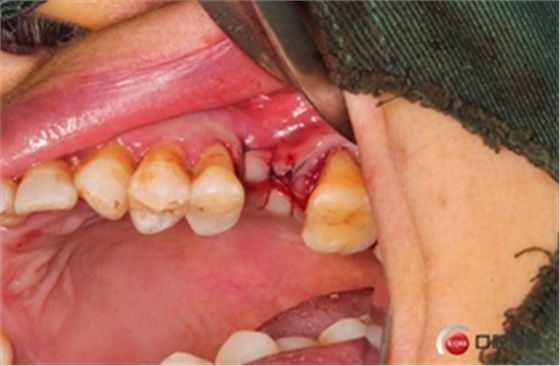

大家好,我是梁老師的助理小依。由于梁老師每天手術(shù)檔期安排較滿,加上經(jīng)常出差講課,沒有時間整理病例 。為了方便大家更及時的了解梁老師最新手術(shù)動態(tài),以后將由我為大家整理并推送梁老師最新經(jīng)典案例。案例文字旁白少,但圖片會盡量完整展示手術(shù)全過程,供大家學(xué)習(xí)參考。有任何問題,可以留言,梁老師會親自為大家解答。感謝大家對梁老師的支持和關(guān)注!

六個月之后